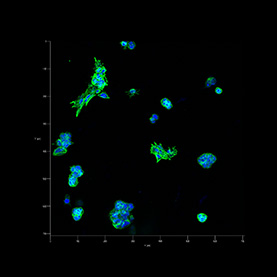

Our bodies have an impressive capacity to heal themselves; unfortunately, the nervous system regenerates much less easily than other vital tissues. Implants of materials that can support or guide the regrowth of cells could help the nervous system recover from injury or disease.

These images reveal the efforts of researchers to coax rat brain cells to grow across a surface of graphene, a material chosen for its toughness, flexibility, and ability to conduct electrical signals. The cells cannot easily implant on the graphene, and in early trials clung to each other instead. In later trials, the addition of the right mix of proteins to the graphene surface enabled cells to implant, grow, and form a healthy, web-like network.

Scientist Collaborator

Hyunjoon Kong Laboratory

Zeiss LSM 700 Confocal Microscope

National Science Foundation